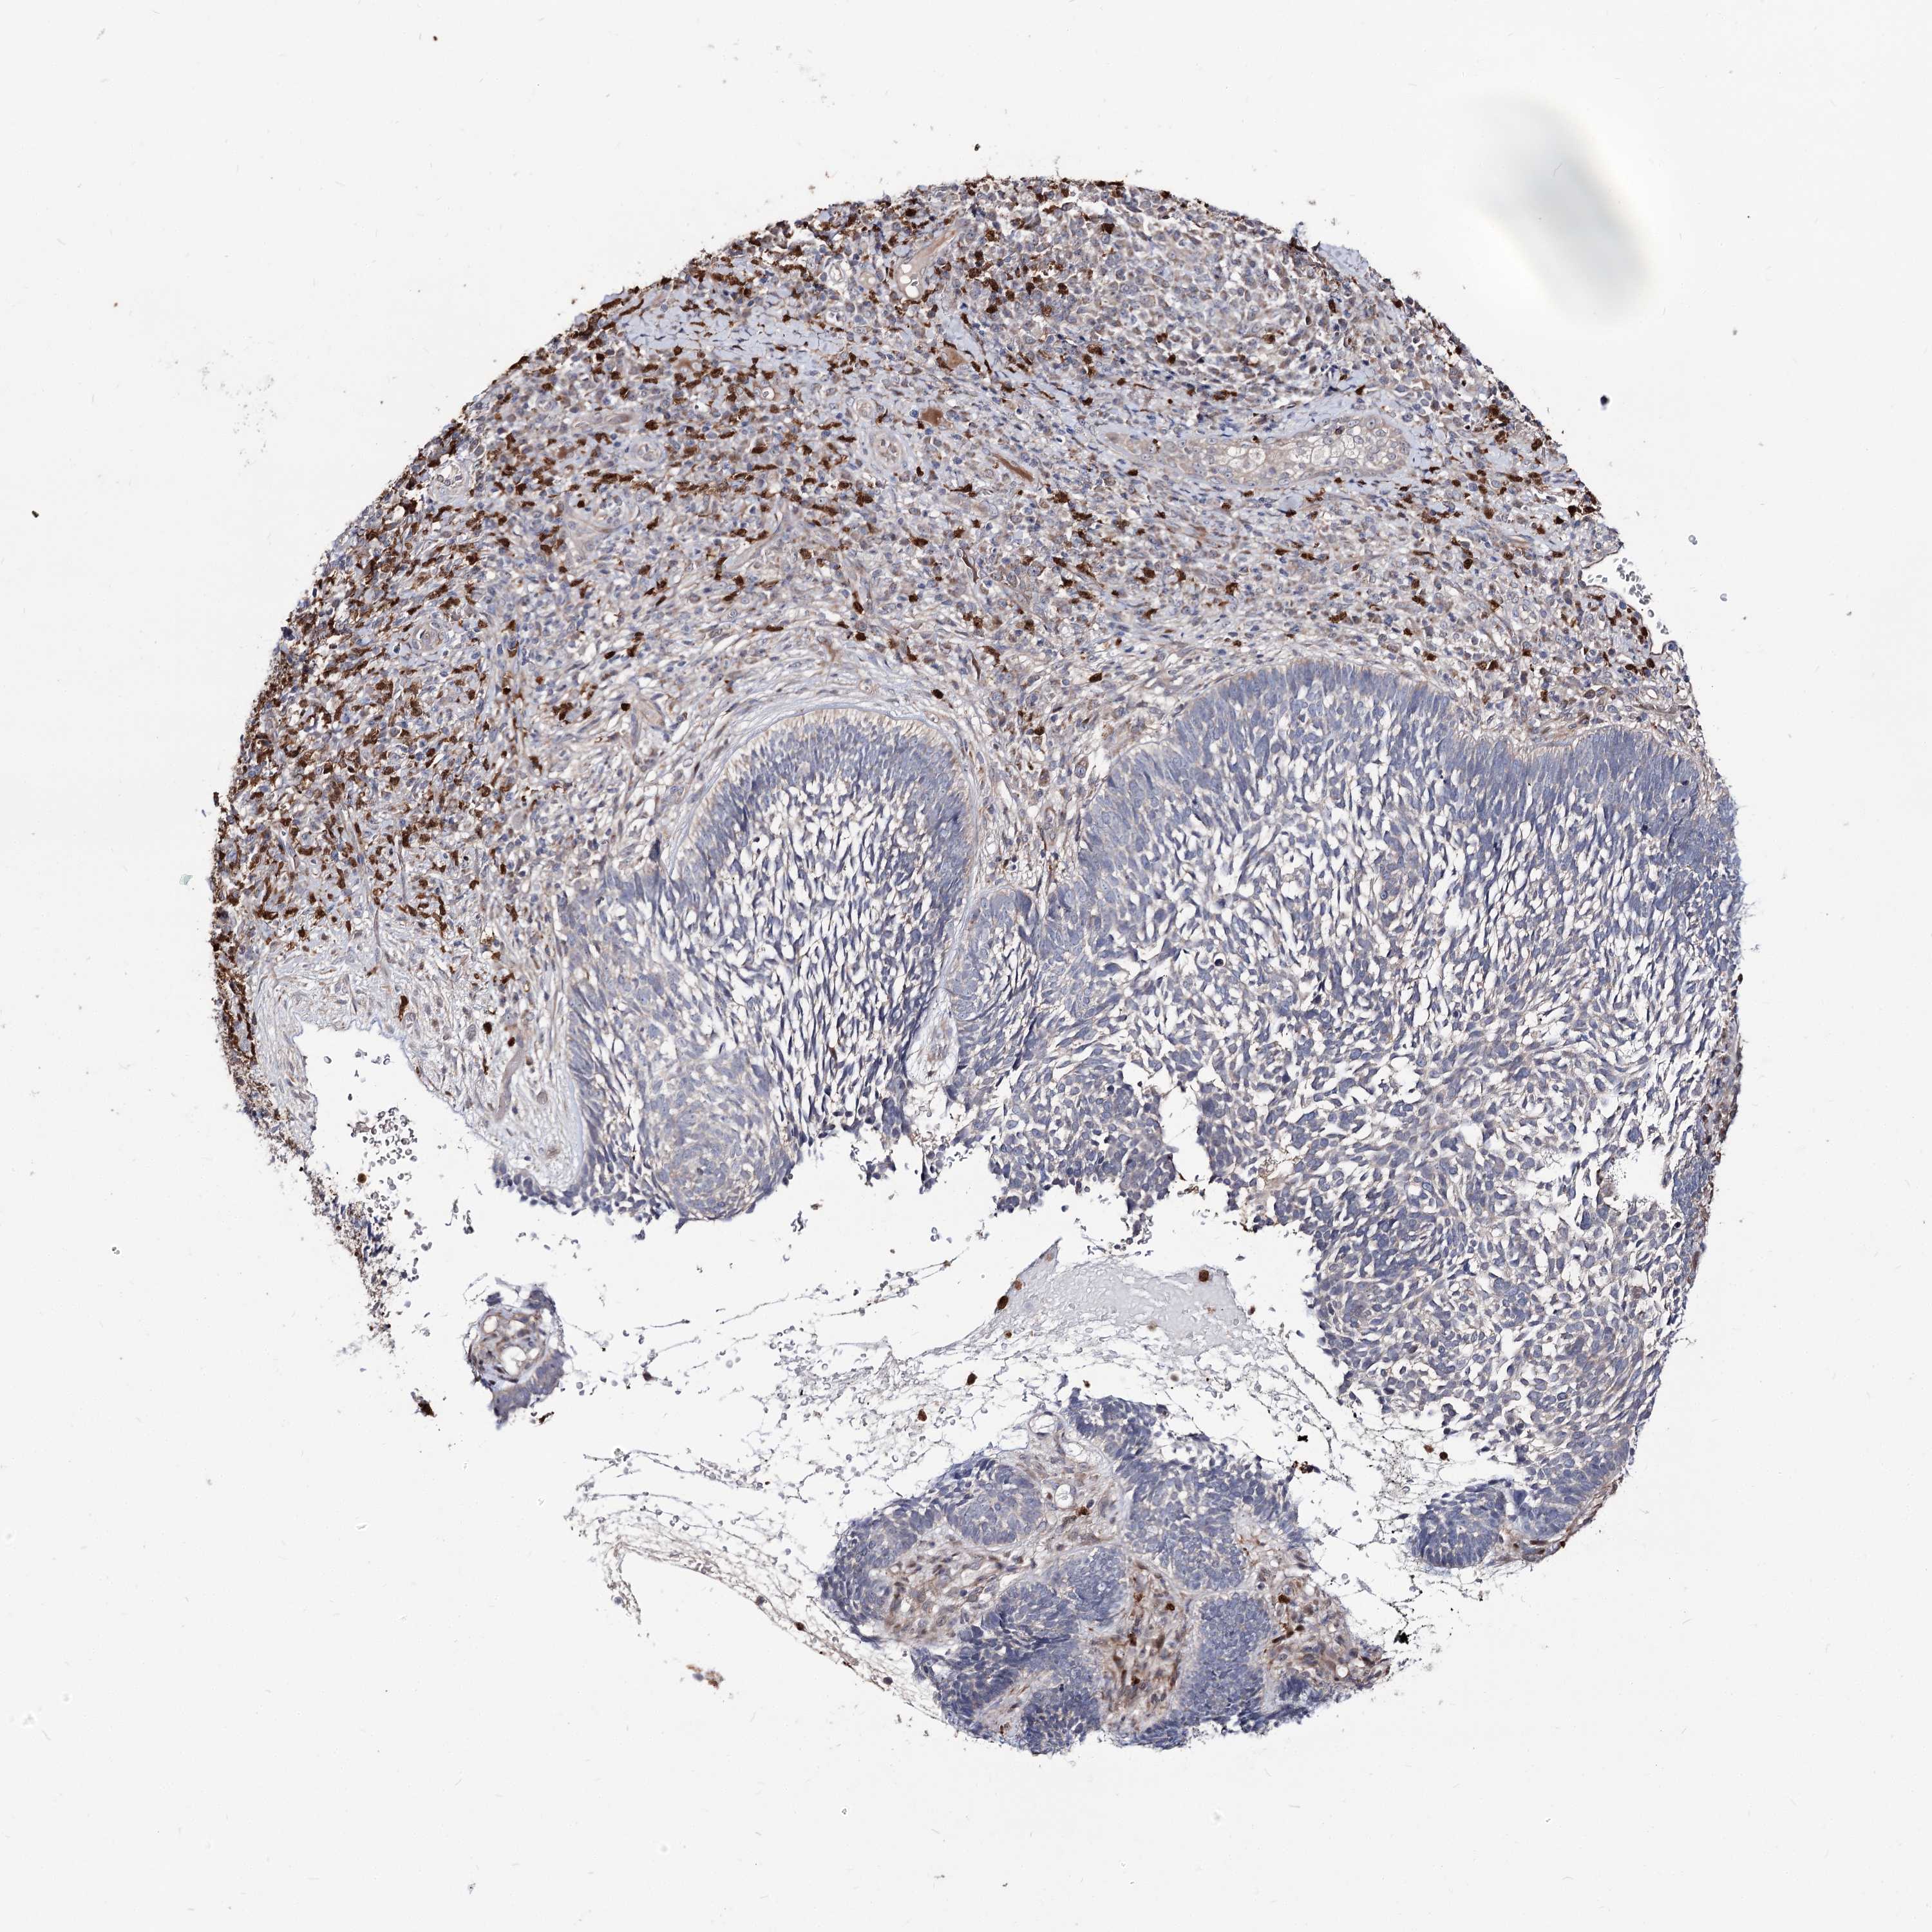

Basal cell and squamous cell cancer

SKIN CANCER - Protein expressioni

A mouse-over function shows sample information and annotation data. Click on an image to view it in a full screen mode. Samples can be filtered based on level of antibody staining by selecting one or several of the following categories: high, medium, low and not detected. The assay and annotation is described here.

Antibody stainingi

Antibody staining in the annotated cell types in the current human tissue is reported as not detected, low, medium, or high, based on conventional immunohistochemistry profiling in selected tissues. This score is based on the combination of the staining intensity and fraction of stained cells.

Each image is clickable and will lead to virtual microscopy that enables deeper exploration of all samples and also displays staining intensity scores, fraction scores and subcellular localization as well as patient and tissue information for each sample.

Antibody HPA038040

Squamous cell carcinoma, metastatic, NOS

Squamous cell carcinoma, NOS